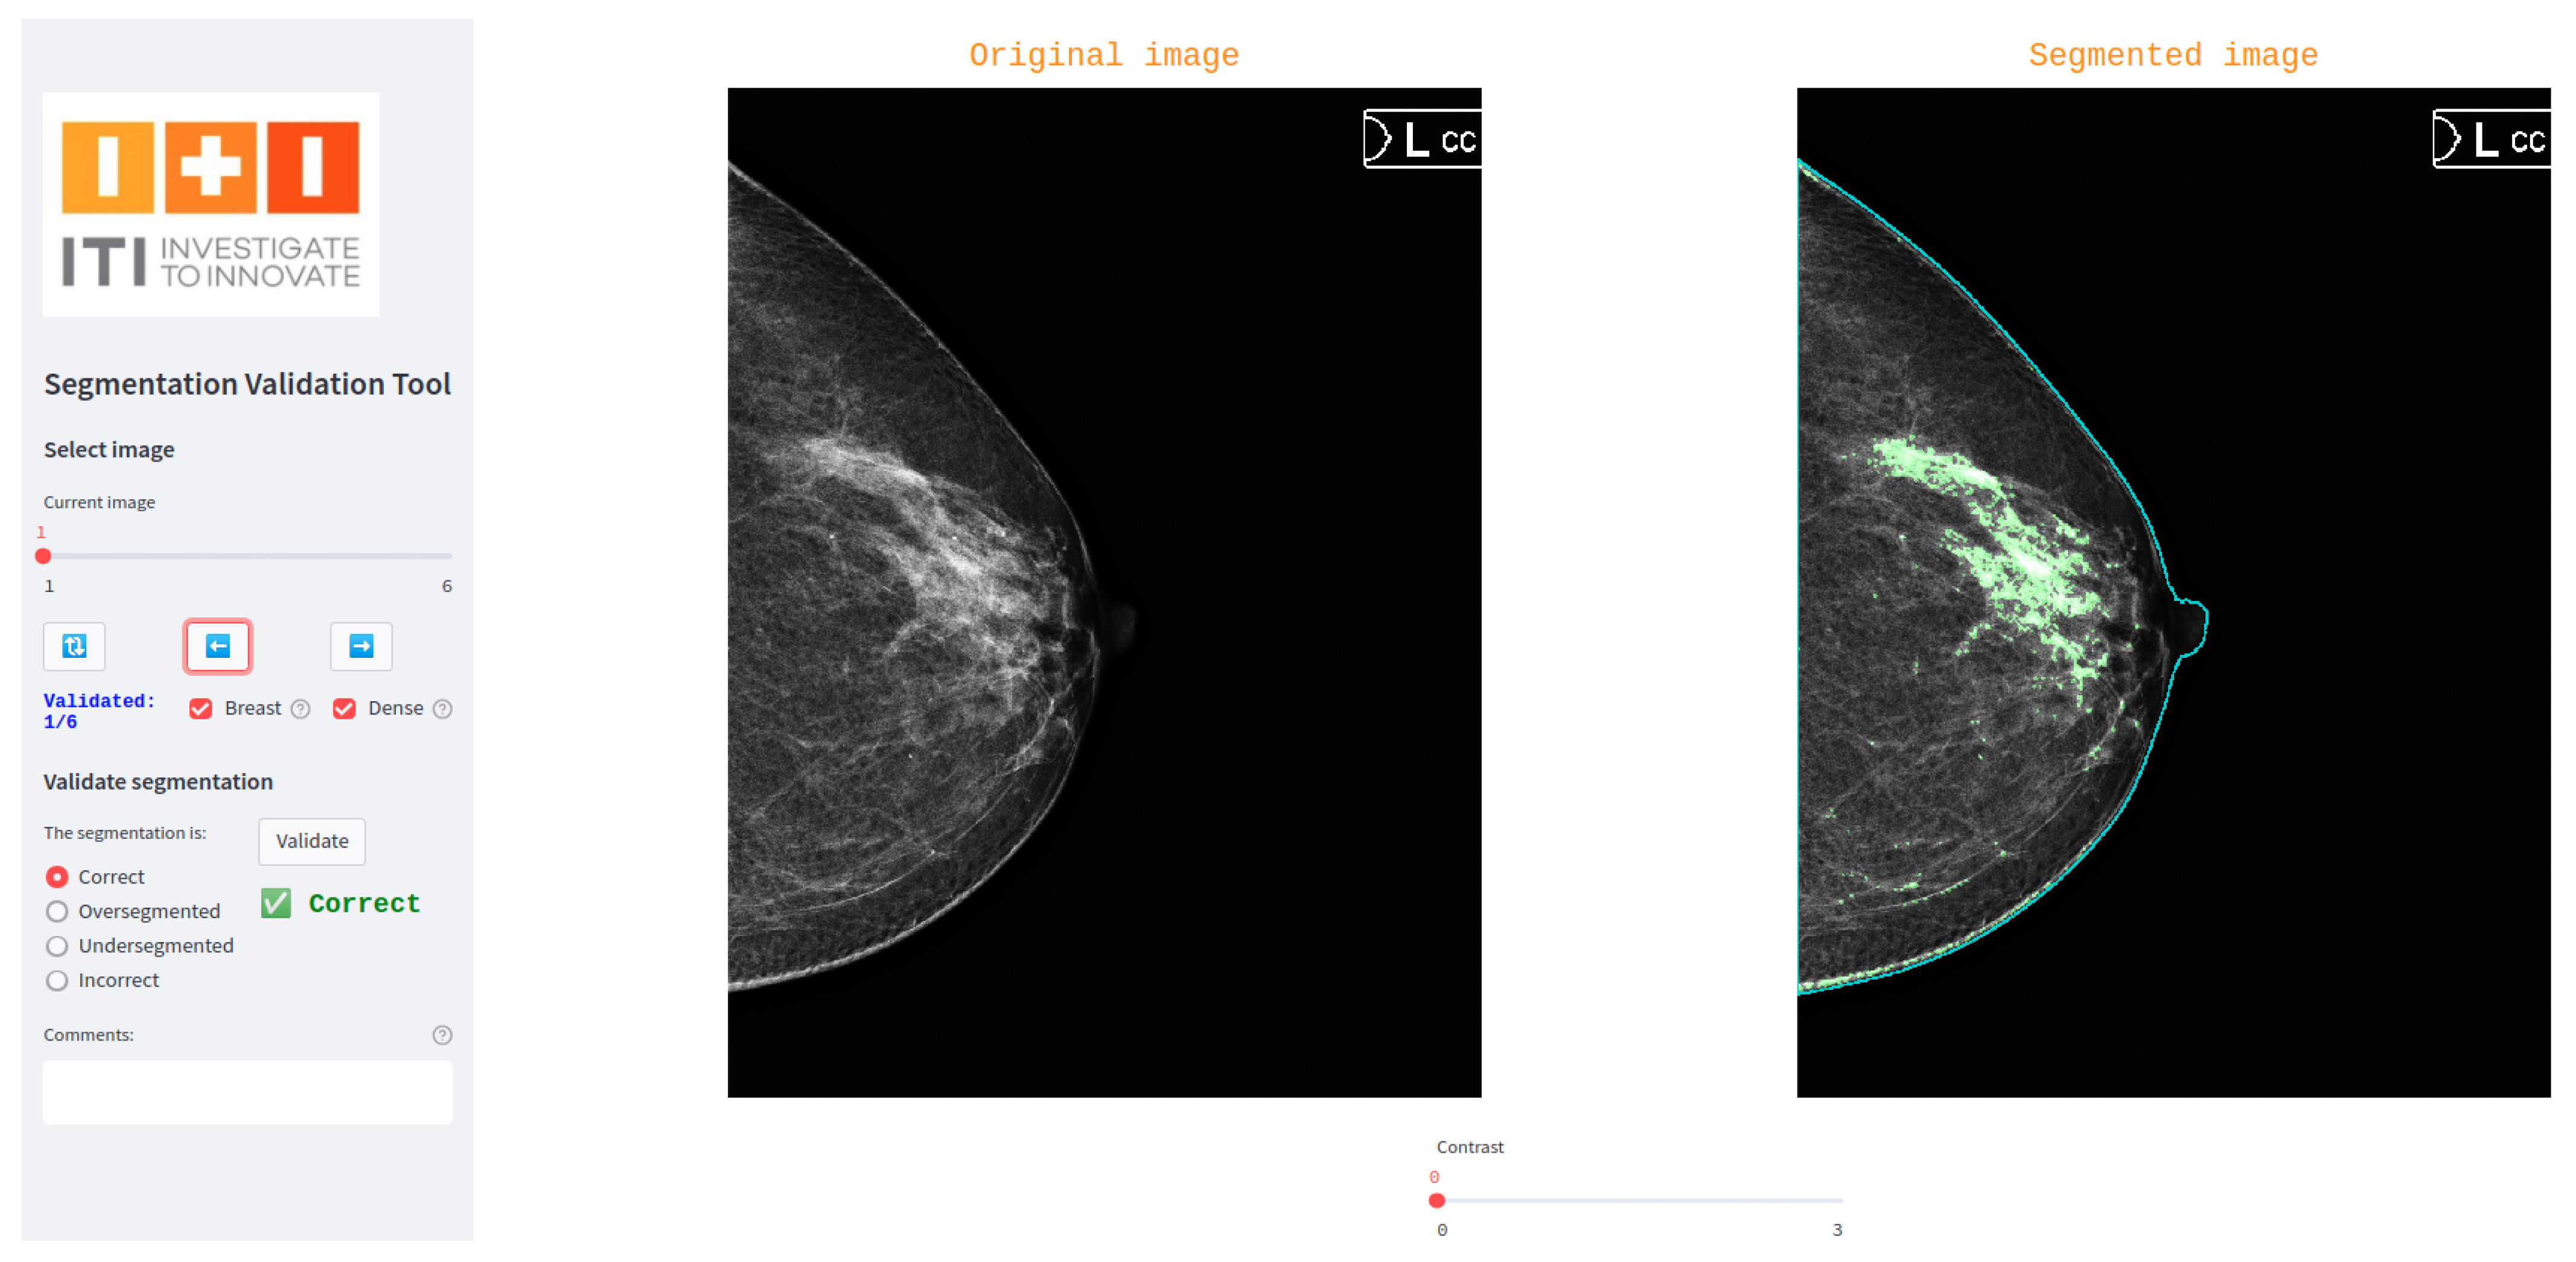

A custom interactive tool was developed to support the three-blind validation strategy by enabling a third specialist (validator) to independently assess segmentation masks. Built using the Python-based Streamlit library [9], the tool provides a user-friendly interface where the validator is presented with one segmentation mask at a time, without any indication of its origin (human or model). The tool randomly determines the order of presentation for segmentations from different sources, ensuring blinding.

For each displayed segmentation, the validator selects one of four predefined categories: correct, oversegmented, undersegmented, or incorrect. The tool also includes a comment box for optional qualitative feedback. This structure supports the standardized quantitative and qualitative evaluation of segmentations while preserving the independence of the assessment.

Figure 2 shows a screenshot of the interface used in our breast dense tissue segmentation use case. In this version, the interface was tailored to display digital mammograms and associated masks. A generalized version of the tool has also been developed and made publicly available via GitLab (https://egitlab.iti.es/praia-salud/segmentation-validation-tool.git, (accessed on 1 May 2025)). This version is designed to be compatible with any segmentation task, as it can be easily configured for different label categories and image modalities.

Figure 2.

Screenshot of the tool used for three-blind validation in the breast dense tissue segmentation use case.